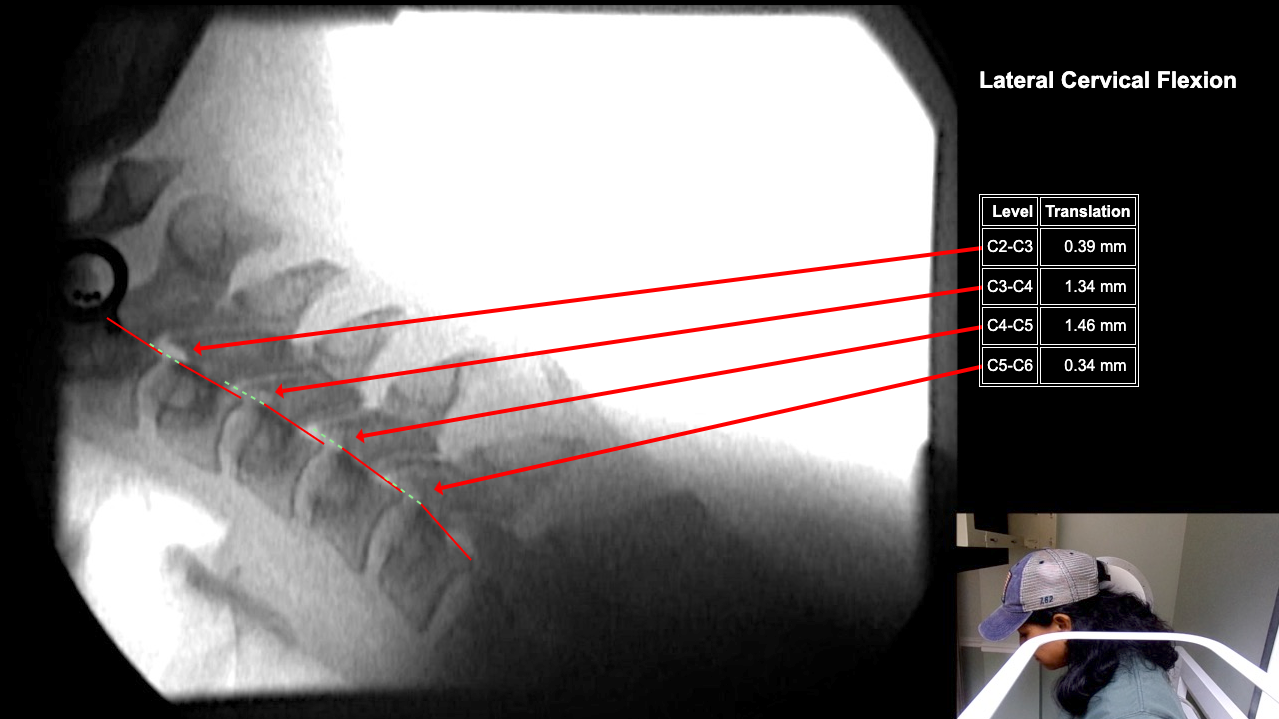

Home > Tamara Tripp 7-3-25